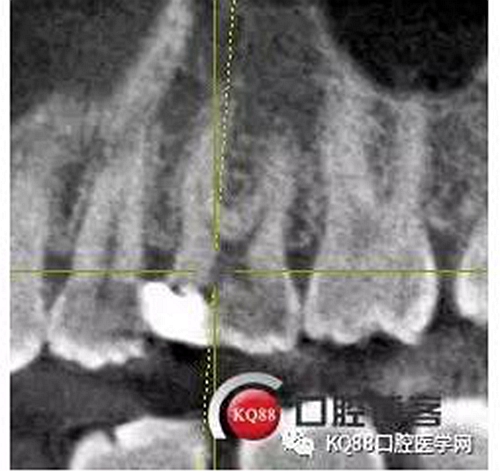

這兩張角度的截圖告訴我們這個牙齒一個典型的Y型根管,髓腔非常巨大,從根管口看,貌似一個根管口,但是根管銼下去以后,會兩個方向角度的分開。因為我們現(xiàn)在都是常規(guī)的機擴與熱牙膠充填,建立直線根管口的暴露就變得非常重要,必須直線視野下操作,機擴才不會發(fā)生扭曲折斷。目前市面上的根管銼有很多,M3,S3等,而此次我使用的是歐羅德卡PLEX軟銼,因為是口腔88贈送我的,所以我就先嘗試的使用了一下,我不會單方面的去評價比別的好,我覺得預備方法對了,都會很不錯,只能說一句這個用起來軟銼對后牙的預備確實不錯。根管預備,常規(guī)我都會先C銼疏通,如果直接15號很有可能會在根尖方形成臺階,以后就很難再下去了,當C銼到達根尖孔后,予以初步測量長度,在用疏通機擴針通入,然后一步步規(guī)范化開始,逐級預備,一個簡單的經(jīng)驗,如果當使用的銼不容易到達根尖時,不要著急,用上一號,繼續(xù),再回來,就可以了,不然形成臺階,就很難操作了,常有人會覺得擴根時,突然發(fā)現(xiàn),下不去了,排除斷針的可能性的話,臺階是最重要的,擴根時,1%次氯酸鈉變沖洗,變預備,防止碎屑推出根尖孔,我沖洗常使用1%次氯酸鈉與蒸餾水,再充填前,會使用EDTA沖洗液去除根管壁油污。